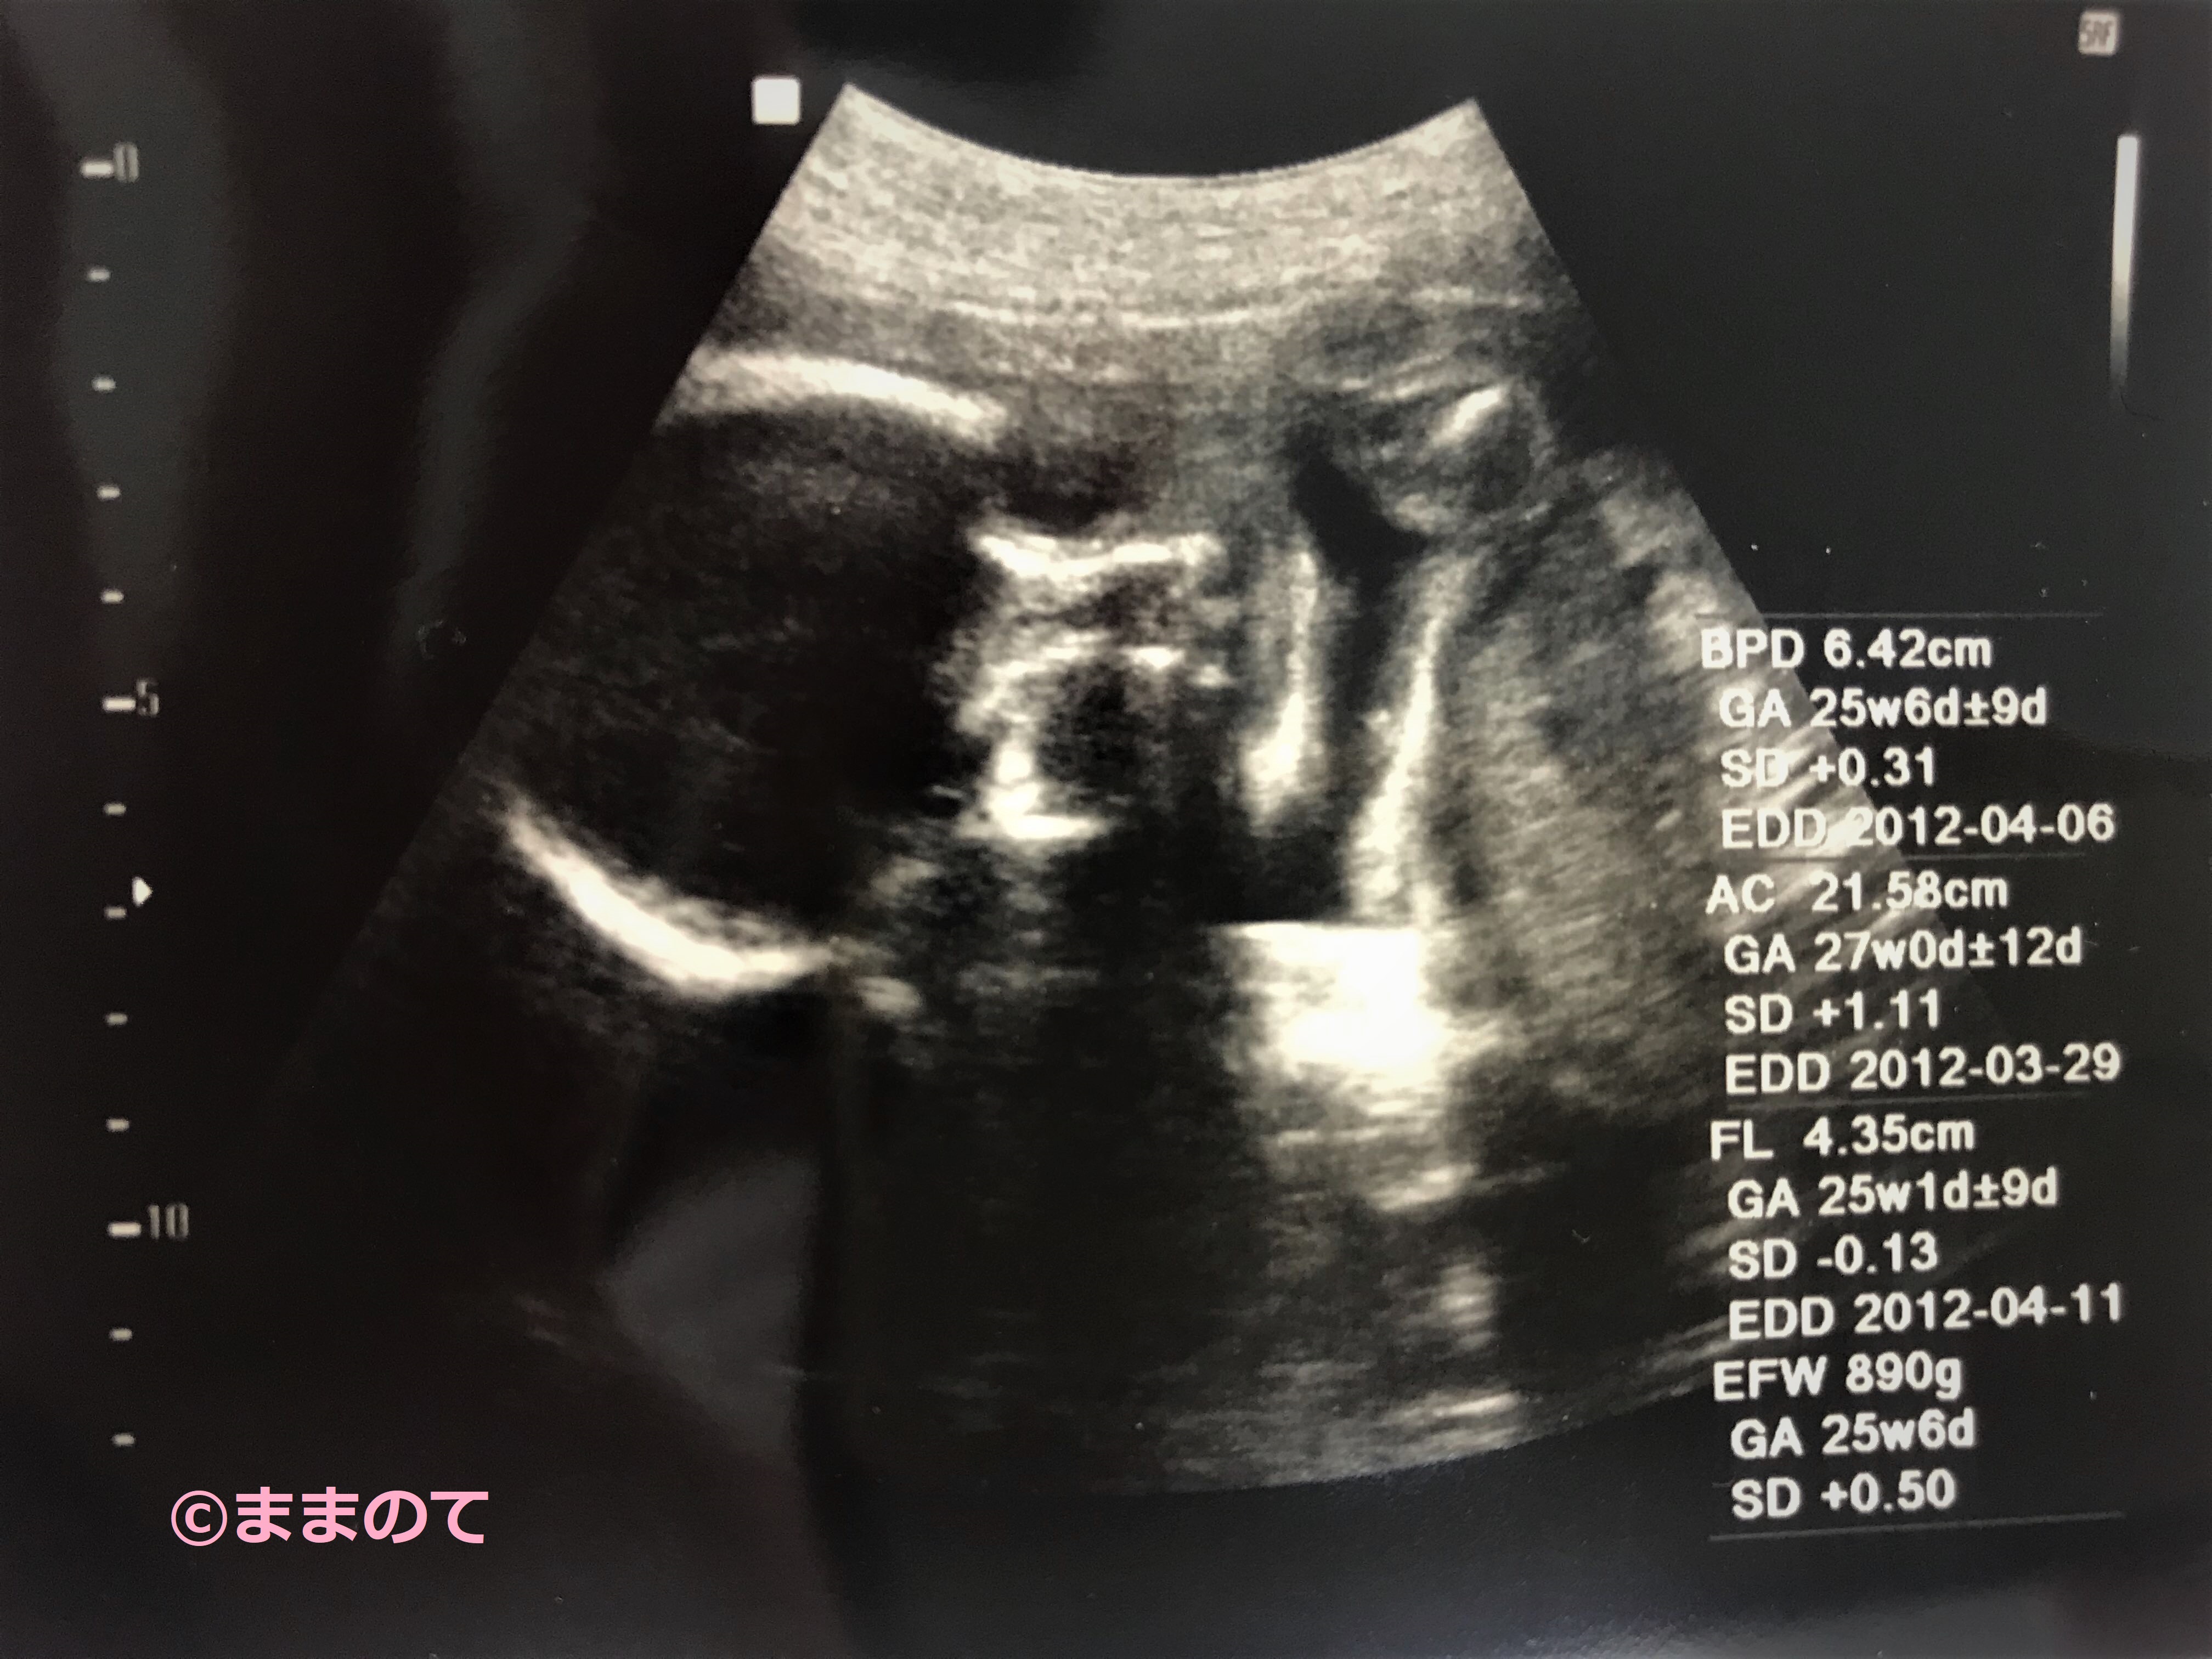

妊娠25週のエコー写真

胎児の外性器も完成に近づいているので、25週のエコー写真で性別がわかることがあるかもしれません。ままのて編集部独自のアンケートによると、妊娠5~7ヶ月ころに性別が判明したママが多いようです。赤ちゃんの姿勢によってはまだ性別がわからない場合もあります。次の妊婦健診を楽しみに待ちましょうね。